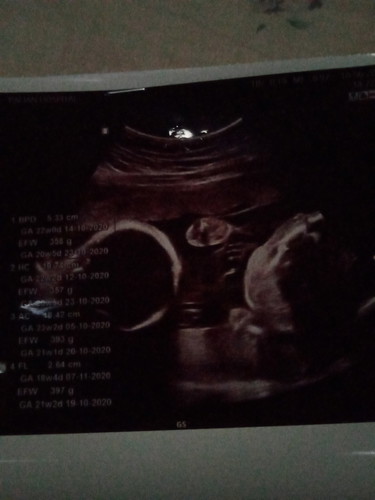

แฝดค่ะท้องได้ประมาณ24w3dน้ำหนักแฝดต้องอยู่ที่เท่าใรคะ

ดูได้ตามตารางเลยค่ะ ใช้ได้ทั้งครรภ์แฝดและครรภ์เดี่ยว